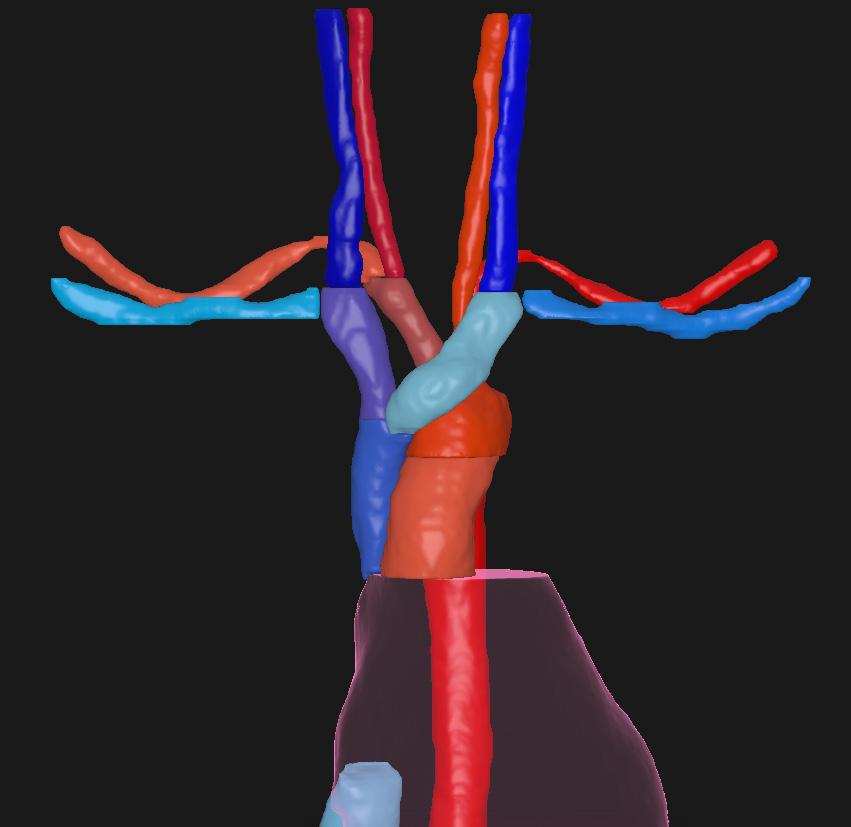

VESSELS CT

STRUCTURES

A_Aorta_Arc A_Subclavian_R

A_Aorta_Asc V_Brachioceph_L

A_Aorta_Desc V_Brachioceph_R

A_Brachiocephls V_Iliac_Ext_L NEW

A_Carotid_Int_L V_Iliac_Ext_R NEW

A_Carotid_Int_R V_Iliac_Int_L NEW

A_Carotid_L V_Iliac_Int_R NEW

A_Carotid_R V_Iliac_L NEW

A_Iliac_Ext_L NEW V_Iliac_R NEW

A_Iliac_Ext_R NEW V_Jugular_Int_L

A_Iliac_Int_L NEW V_Jugular_Int_R

A_Iliac_Int_R NEW V_Subclavian_L

A_Iliac_L NEW V_Subclavian_R

A_Iliac_R NEW V_Venacava_I IMPROVED

A_Subclavian_L V_Venacava_S